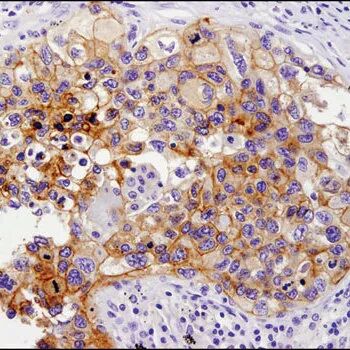

使用 ICOS (D1K2T™) Rabbit mAb 对石蜡包埋的人结肠癌细胞进行免疫组织化学分析。